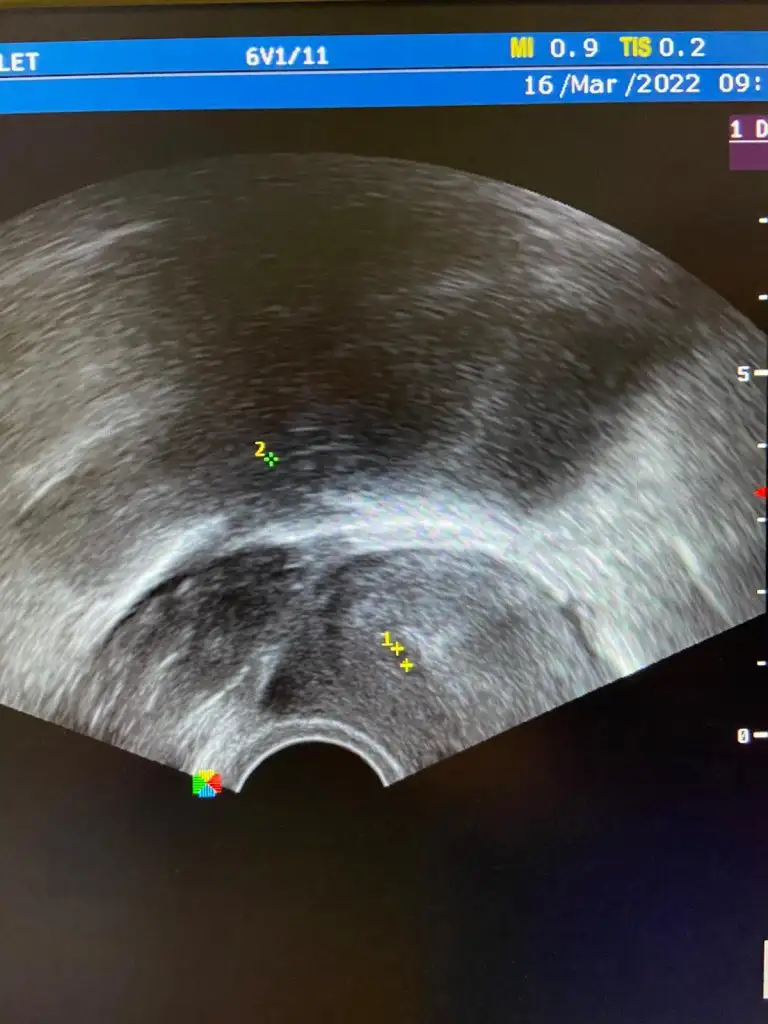

Orada 2 kese mi var canım? Doktor 2 tane işaretleme yapmış :)) hadi gözün aydın darısı kalp atışını duymana inşallahKızlar ben geldim kese göründü :)

tatlım hiç bilmiyorum yaaa birsey söylemedi hiç bana bende anlamadım. hafta sonu özele gidicemOrada 2 kese mi var canım? Doktor 2 tane işaretleme yapmış :)) hadi gözün aydın darısı kalp atışını duymana inşallah